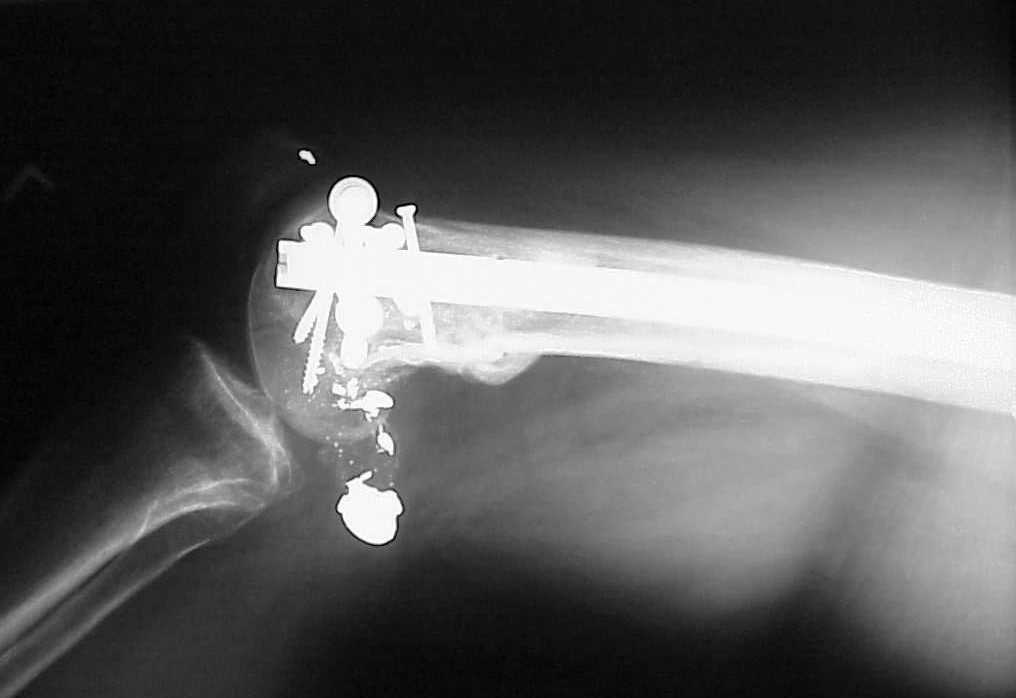

See attached case that was done several years ago before LISS. He had comminuted trochlea and anterior blocking screws were used to prevent anterior IMN cut-out.

Since it was done closed the shaft will heal or at worst need an exchange IMN.

Мы пошли на операцию с планом попытаться сделать закрытый интрамедулярный, а не получится - сделать аппаратом. Посчитали, что получилось, хотя на еженедельной конференции ожидаются некоторые проблемы с объяснениями ;-)

Насчет стабильности для ранней нагрузки, конечно, сомнительно, но при таком повреждении ранняя нагрузка противопоказана в любом случае. Для ранних движений Должно хватить. Снимки в следующем сообщении.